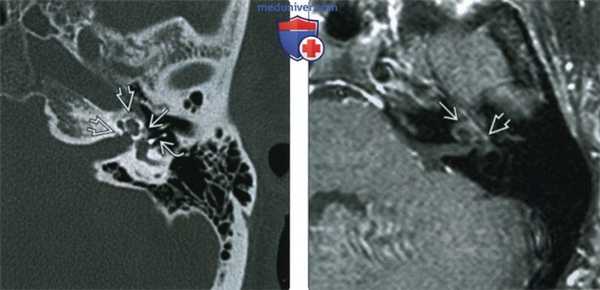

Рис 1. Активная форма отосклероза: плотность очагов +300 - +800 ед. Н.

При смешанных формах, выявленных по КТ височных костей, помимо фенестральной локализации очагов отоспонгиоза или отосклероза, определяются участки пониженной плотности капсулы лабиринта, окружающие улитку, распространяющиеся на область круглого окна, иногда до дна внутреннего слухового прохода (рис. 2). При смешанной форме распространения очагов отоспонгиоза или отосклероза, выявленных по КТ височных костей, по данным ТПА определяется смешанная форма тугоухости (1-2 ст.).

Рис. 2. Смешанная форма отосклероза (плотность очагов отоспонгиоза +300- +800 ед. Н).

При кохлеарном отосклерозе, в начальной его стадии в костной капсуле лабиринта, окружающей улитку, выявляются участки пониженной плотности +1500- +1100 ед. H. При умеренно выраженной активной стадии - в костной капсуле лабиринта, вокруг базального и апикального завитков улитки определяются хорошо видимые на томограммах участки пониженной плотности +1000- +600 ед. H, часто распространяющиеся на область круглого окна и могут достигать дна внутреннего слухового прохода и горизонтальных полукружных каналов (рис. 3).

Рис. 3. Кохлеарная форма отосклерза (плотоность очагов + 600 - +800 ед. Н).

На стадии далеко зашедшего кохлеарного отосклероза выявляется деминерализация костной капсулы ушного лабиринта на уровне базального и апикального витков улитки. Также изменения могут достигать преддверия и полукружных каналов. Плотность на этой стадии колеблется от +300 до +1200 ед. H. На этой стадии развития отосклероза могут определяться явления костной облитерации структур лабиринта. Наиболее часто явления облитерации по данным КТ височных костей выявляются в базальном завитке улитке и горизонтальном полукружном канале (табл. 1).